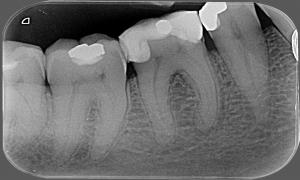

Pred zákrokom

Chrup s amalgámovými výplňami

Po zákroku

Výmena amalgámových výplní fotokompozitnými plombami s estetickým a anatomickým tvarom zubu